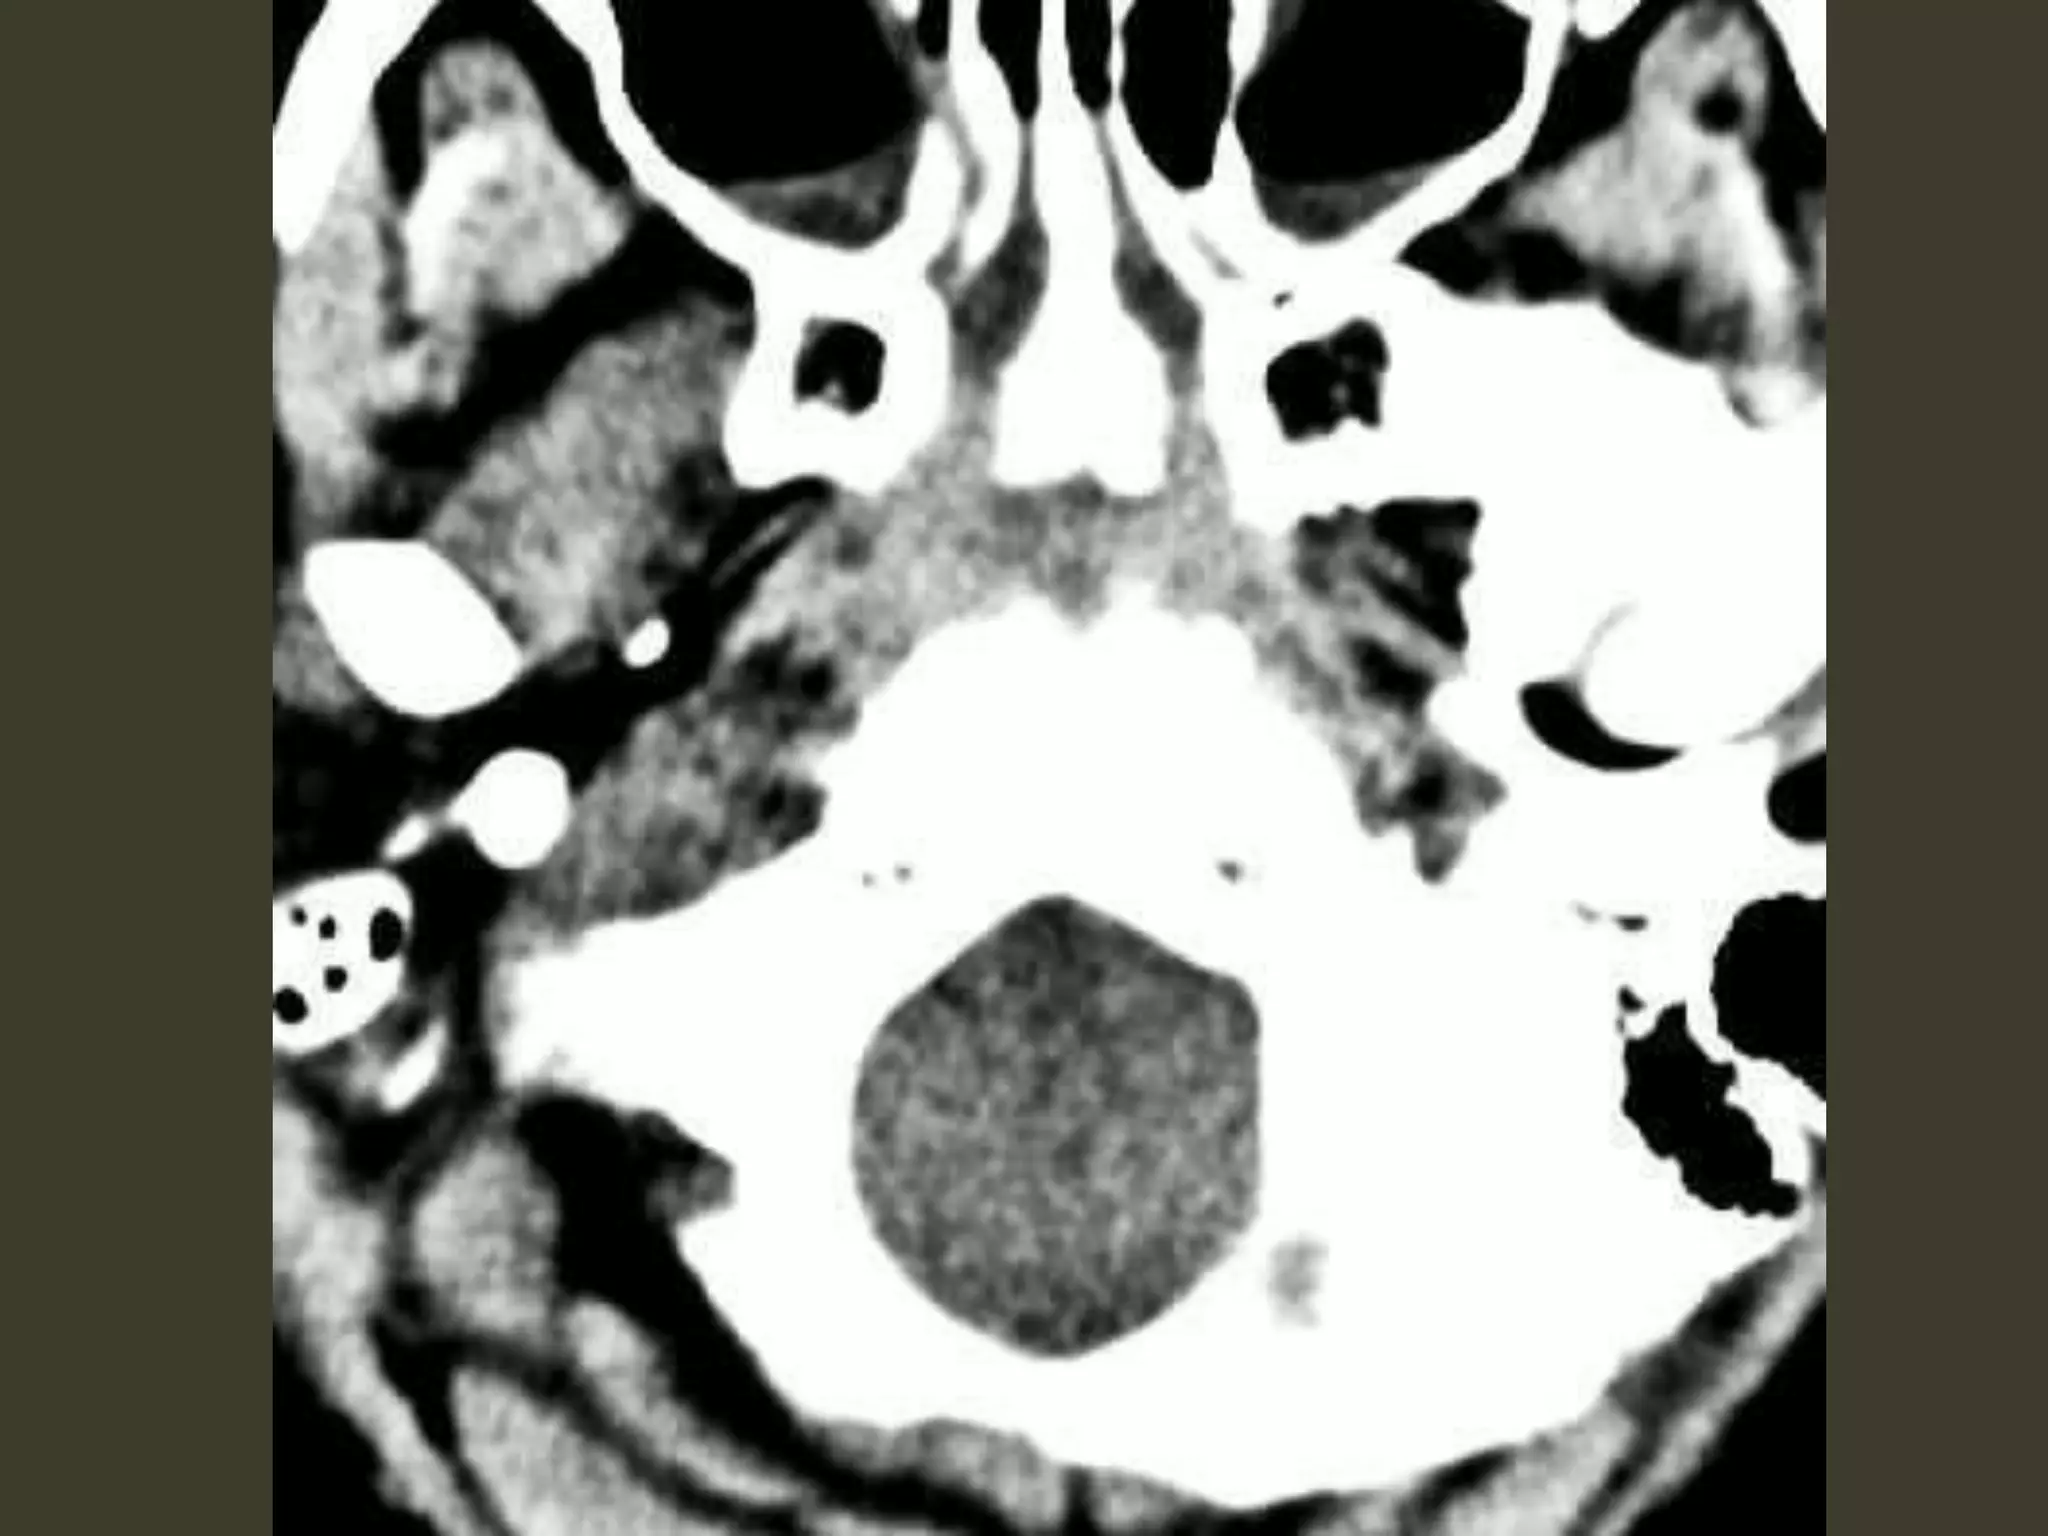

unilateral DTH: imaging early uncusis displaced medially Ipsilateral aspect of the suprasellar cistern effaced Ipsilateral prepontine + cerebellopontine angle cistern enlarged

Descending transtentorial herniation As DTHincreases hippocampus also herniates medially quadrigeminal cistern compression midbrain pushed toward the opposite side of the incisura

Descending transtentorial herniation severe cases entiresuprasellar and quadrigeminal cisterns are effaced. The temporal horn can even be displaced almost into the midline